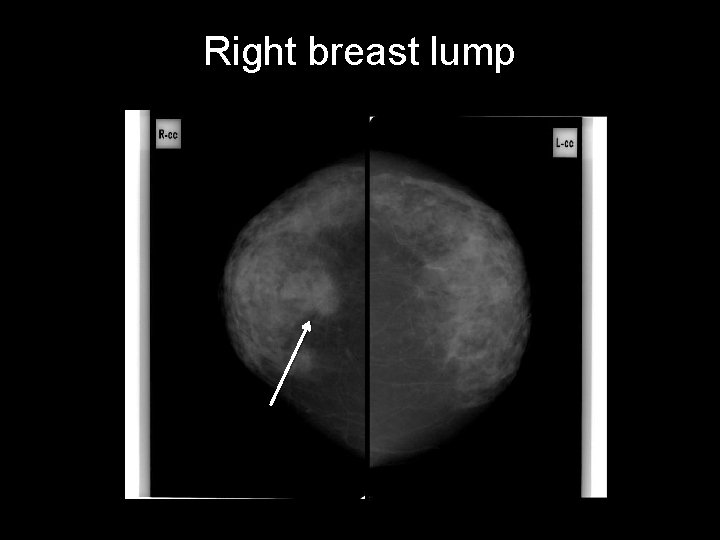

Right breast lump CASE 2 • • Right breast lump Age: 71 years old Gender: Female Race: Middle eastern • First study? – Ultrasound – Mammography – MRI w contrast

Right breast lump

Right breast lump lymph nodes • speculated opacity at the middle of the lower part • focus of macrocalcification adjacent to the mass • Bilateral axillary lymph nodes microcalcifications mass